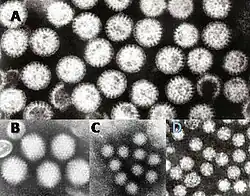

- ...that a toddler with a syndrome of rash (pictured), arthralgia/arthritis, abdominal pain and renal disease, preceded by a viral upper respiratory tract infection, is likely to have Henoch-Schönlein purpura?